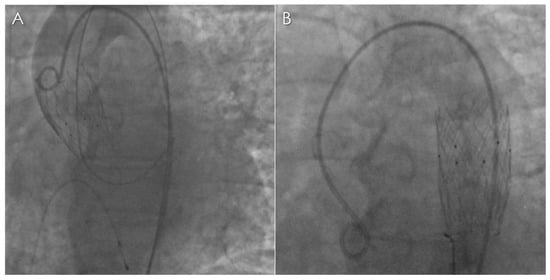

Spectral CT Imaging of Prosthetic Valve Embolization after Transcatheter Aortic Valve Implantation

D’Angelo, T.; Vizzari, G.; Lanzafame, L.R.M.; Pergolizzi, F.; Mazziotti, S.; Gaeta, M.; Costa, F.; Di Bella, G.; Vogl, T.J.; Booz, C.; et al. Spectral CT Imaging of Prosthetic Valve Embolization after Transcatheter Aortic Valve Implantation. Diagnostics 2023, 13, 678. https://doi.org/10.3390/diagnostics13040678